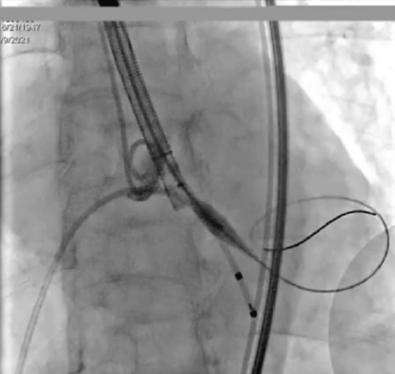

输送系统输送至窦底,行主动脉根部造影,借助无冠窦猪尾造影定位,由于该患者基础心率较缓慢,瓣膜无起搏顺利释放。

释放